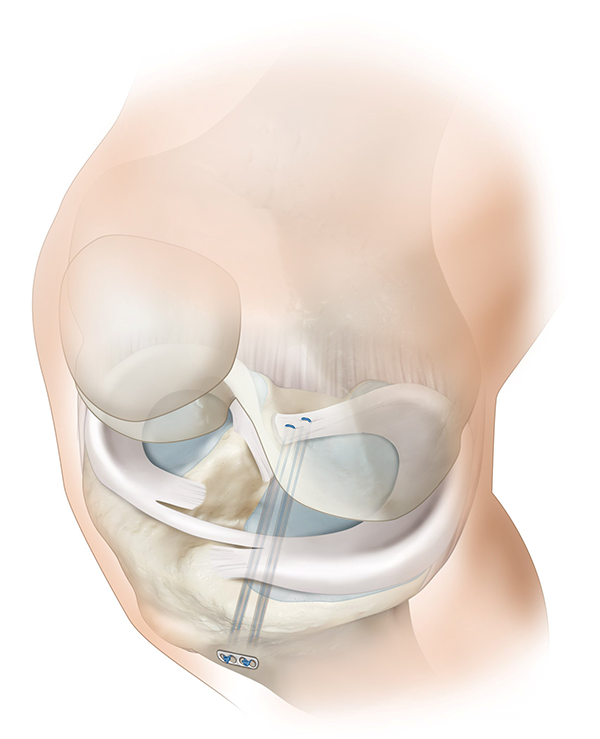

Para restaurar la función del menisco después de los desgarros de la raíz se utiliza con mayor frecuencia la técnica de reparación transósea, e implica el paso de dos suturas simples a través del borde lesionado y luego a través de túneles óseos para su fijación en la tibia proximal (fig. 5).6, 20, 21 Después de pasar las suturas a través de dos túneles tibiales, se atan sobre un puente óseo o un botón quirúrgico6, 22, 23 (fig. 6). La técnica de reparación de dos túneles permite obtener una amplia huella anatómica para maximizar el potencial de curación y la liberación de factores biológicos para mejorar las chances de cicatrización de la raíz del menisco.9, 24-30

Figura 5: Imagen esquemática en la cual se detalla la localización y dirección de los dos túneles óseos en tibia proximal para el paso posterior de las suturas.

Figura 6: Imagen esquemática en la cual se representan las suturas pasadas por los túneles óseos y atadas sobre un botón quirúrgico.